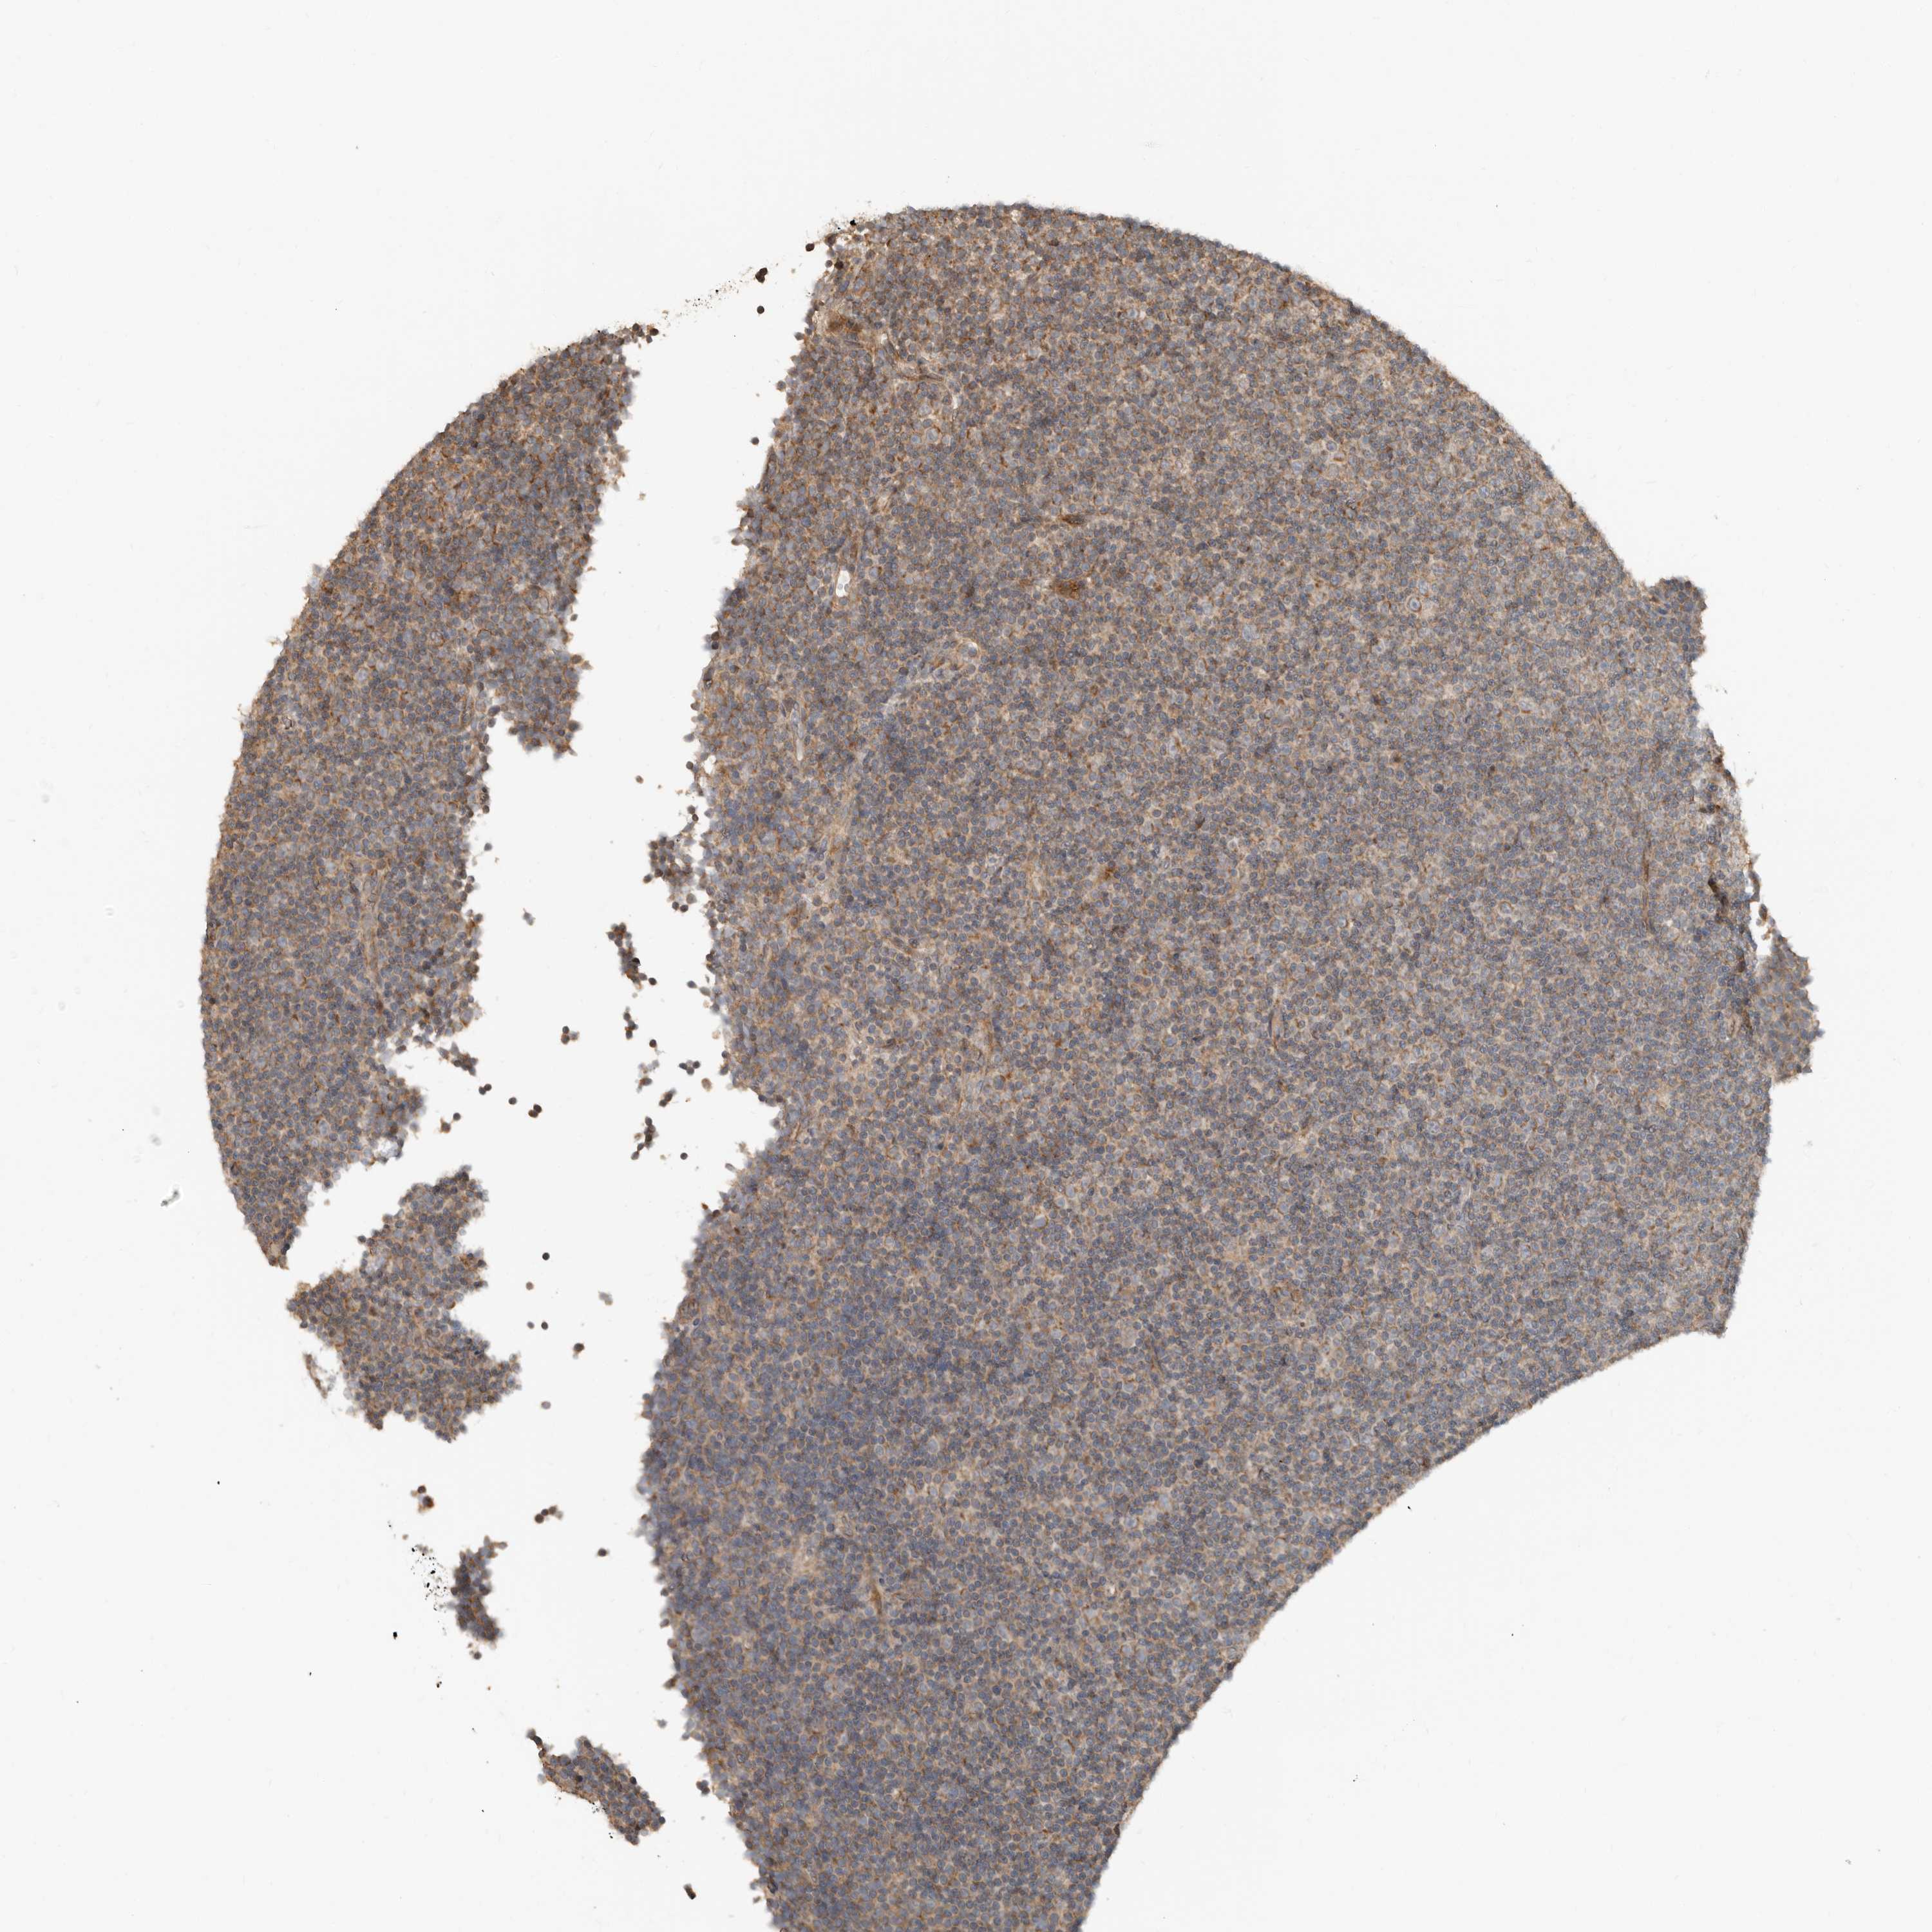

CANCER LYMPHOMA Show tissue menu

LYMPHOMA - Protein expressioni

A mouse-over function shows sample information and annotation data. Click on an image to view it in a full screen mode. Samples can be filtered based on level of antibody staining by selecting one or several of the following categories: high, medium, low and not detected. The assay and annotation is described here.

Each image is clickable and will lead to virtual microscopy that enables deeper exploration of all samples and also displays staining intensity scores, fraction scores and subcellular localization as well as patient and tissue information for each sample.

Antibody HPA028907

Staining

High

Medium

Low

Not detected

Intensity

Strong

Moderate

Weak

Negative

Quantity

>75%

75%-25%

<25%

None

Location

Nuclear

Cytoplasmic/membranous

Cytoplasmic/membranous,nuclear

Hodgkin's disease, NOS

Malignant lymphoma, non-Hodgkin's type, High grade

Malignant lymphoma, non-Hodgkin's type, Low grade